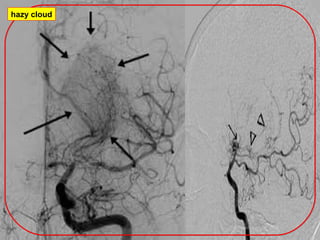

1-Cerebral angiography should demonstrate the following findings:

(a) Stenosis or occlusion at the terminal portion of the ICA and/or

the proximal portion of the ACA and/or MCA.

(b) Abnormal vascular networks in the vicinity of the occlusive or

stenotic lesions.

(c) These findings should be present bilaterally.

Puff of smoke

DSA

LT MCA&ACA

hazy cloud

Stenosis

No ACA

moyamoya.